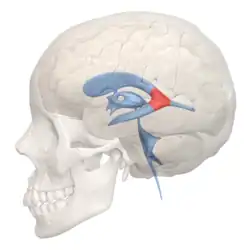

Scheme showing relations of the ventricles to the surface of the brain; oriented facing left. | |

Position of lateral ventricles (shown in red)

Position of lateral ventricles (shown in red) -